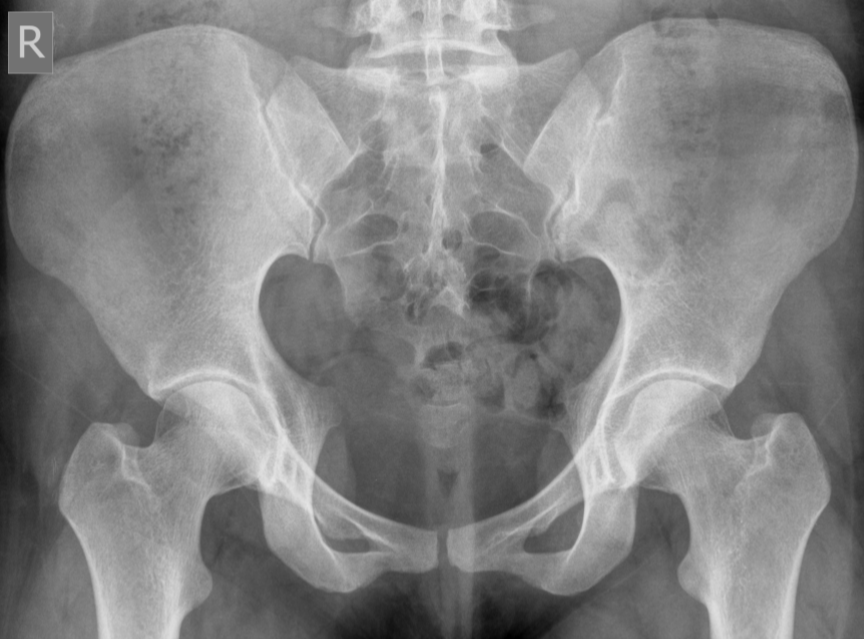

Pincer morphology femoroacetabular impingement (FAI)